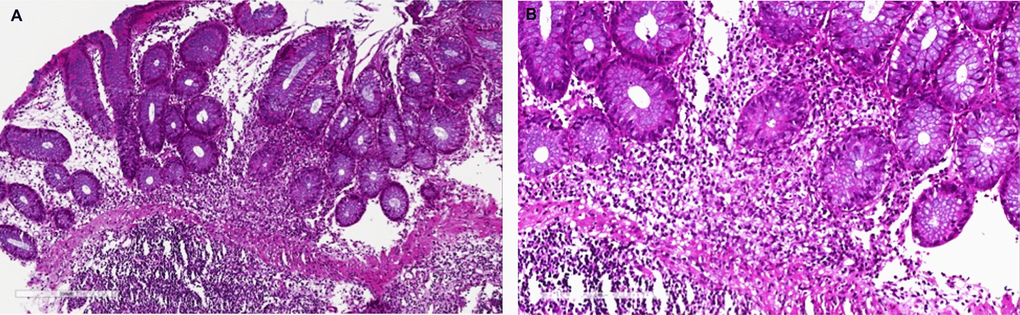

Nineteen patients (14.1%) developed a post-transplant colitis (Table 4). Eight patients (6%) presented a MPA/colitis: mean age was 55.1± 11.3, female patients were 50%, and all patients presented with diarrhea. The mean time from transplant to MPA-related diarrhea onset was 84.7±34.3 months. All patients but one had positive FIT, and mean FCP was 1716±675.3 mcg/g. Colonoscopic findings included erosions, colonic ulcers and hyperemia (Figure 1). Histological findings revealed a mild to severe eosinophils and plasma cells infiltrate with cryptic abscesses (Figures 2, 3). All patients had a reduction of MPA dosage: at mean follow up of 31±9.7 months, 5 patients had a complete resolution of diarrhea after MPA reduction, while 3 patients had only a mild improvement. In patients with clinical resolution mean FCP was 320±121 mcg/g compared to patients without complete resolution who exhibited a mean FCP of 745±223.4 mcg/g (p = 0.065).

Figure 2. Mycophenolic acid colitis. Histological evaluation at 10x (A) and 20x (B). Colon biopsy retrieved from right colon during diagnostic colonoscopy shows (A) a severe eosinophils and plasma cells infiltrate of the submucosal layer (magnification 10x), (B) confirmed at higher magnification (20x).

Figure 3. Mycophenolate mofetil colitis. Histological examination. Biopsy of right colon: (A) severe eosinophils, lymphocytes and plasma cells infiltrate (10x), with (B) severe cryptitis (20x, white arrow) and cell apoptosis (black arrow).